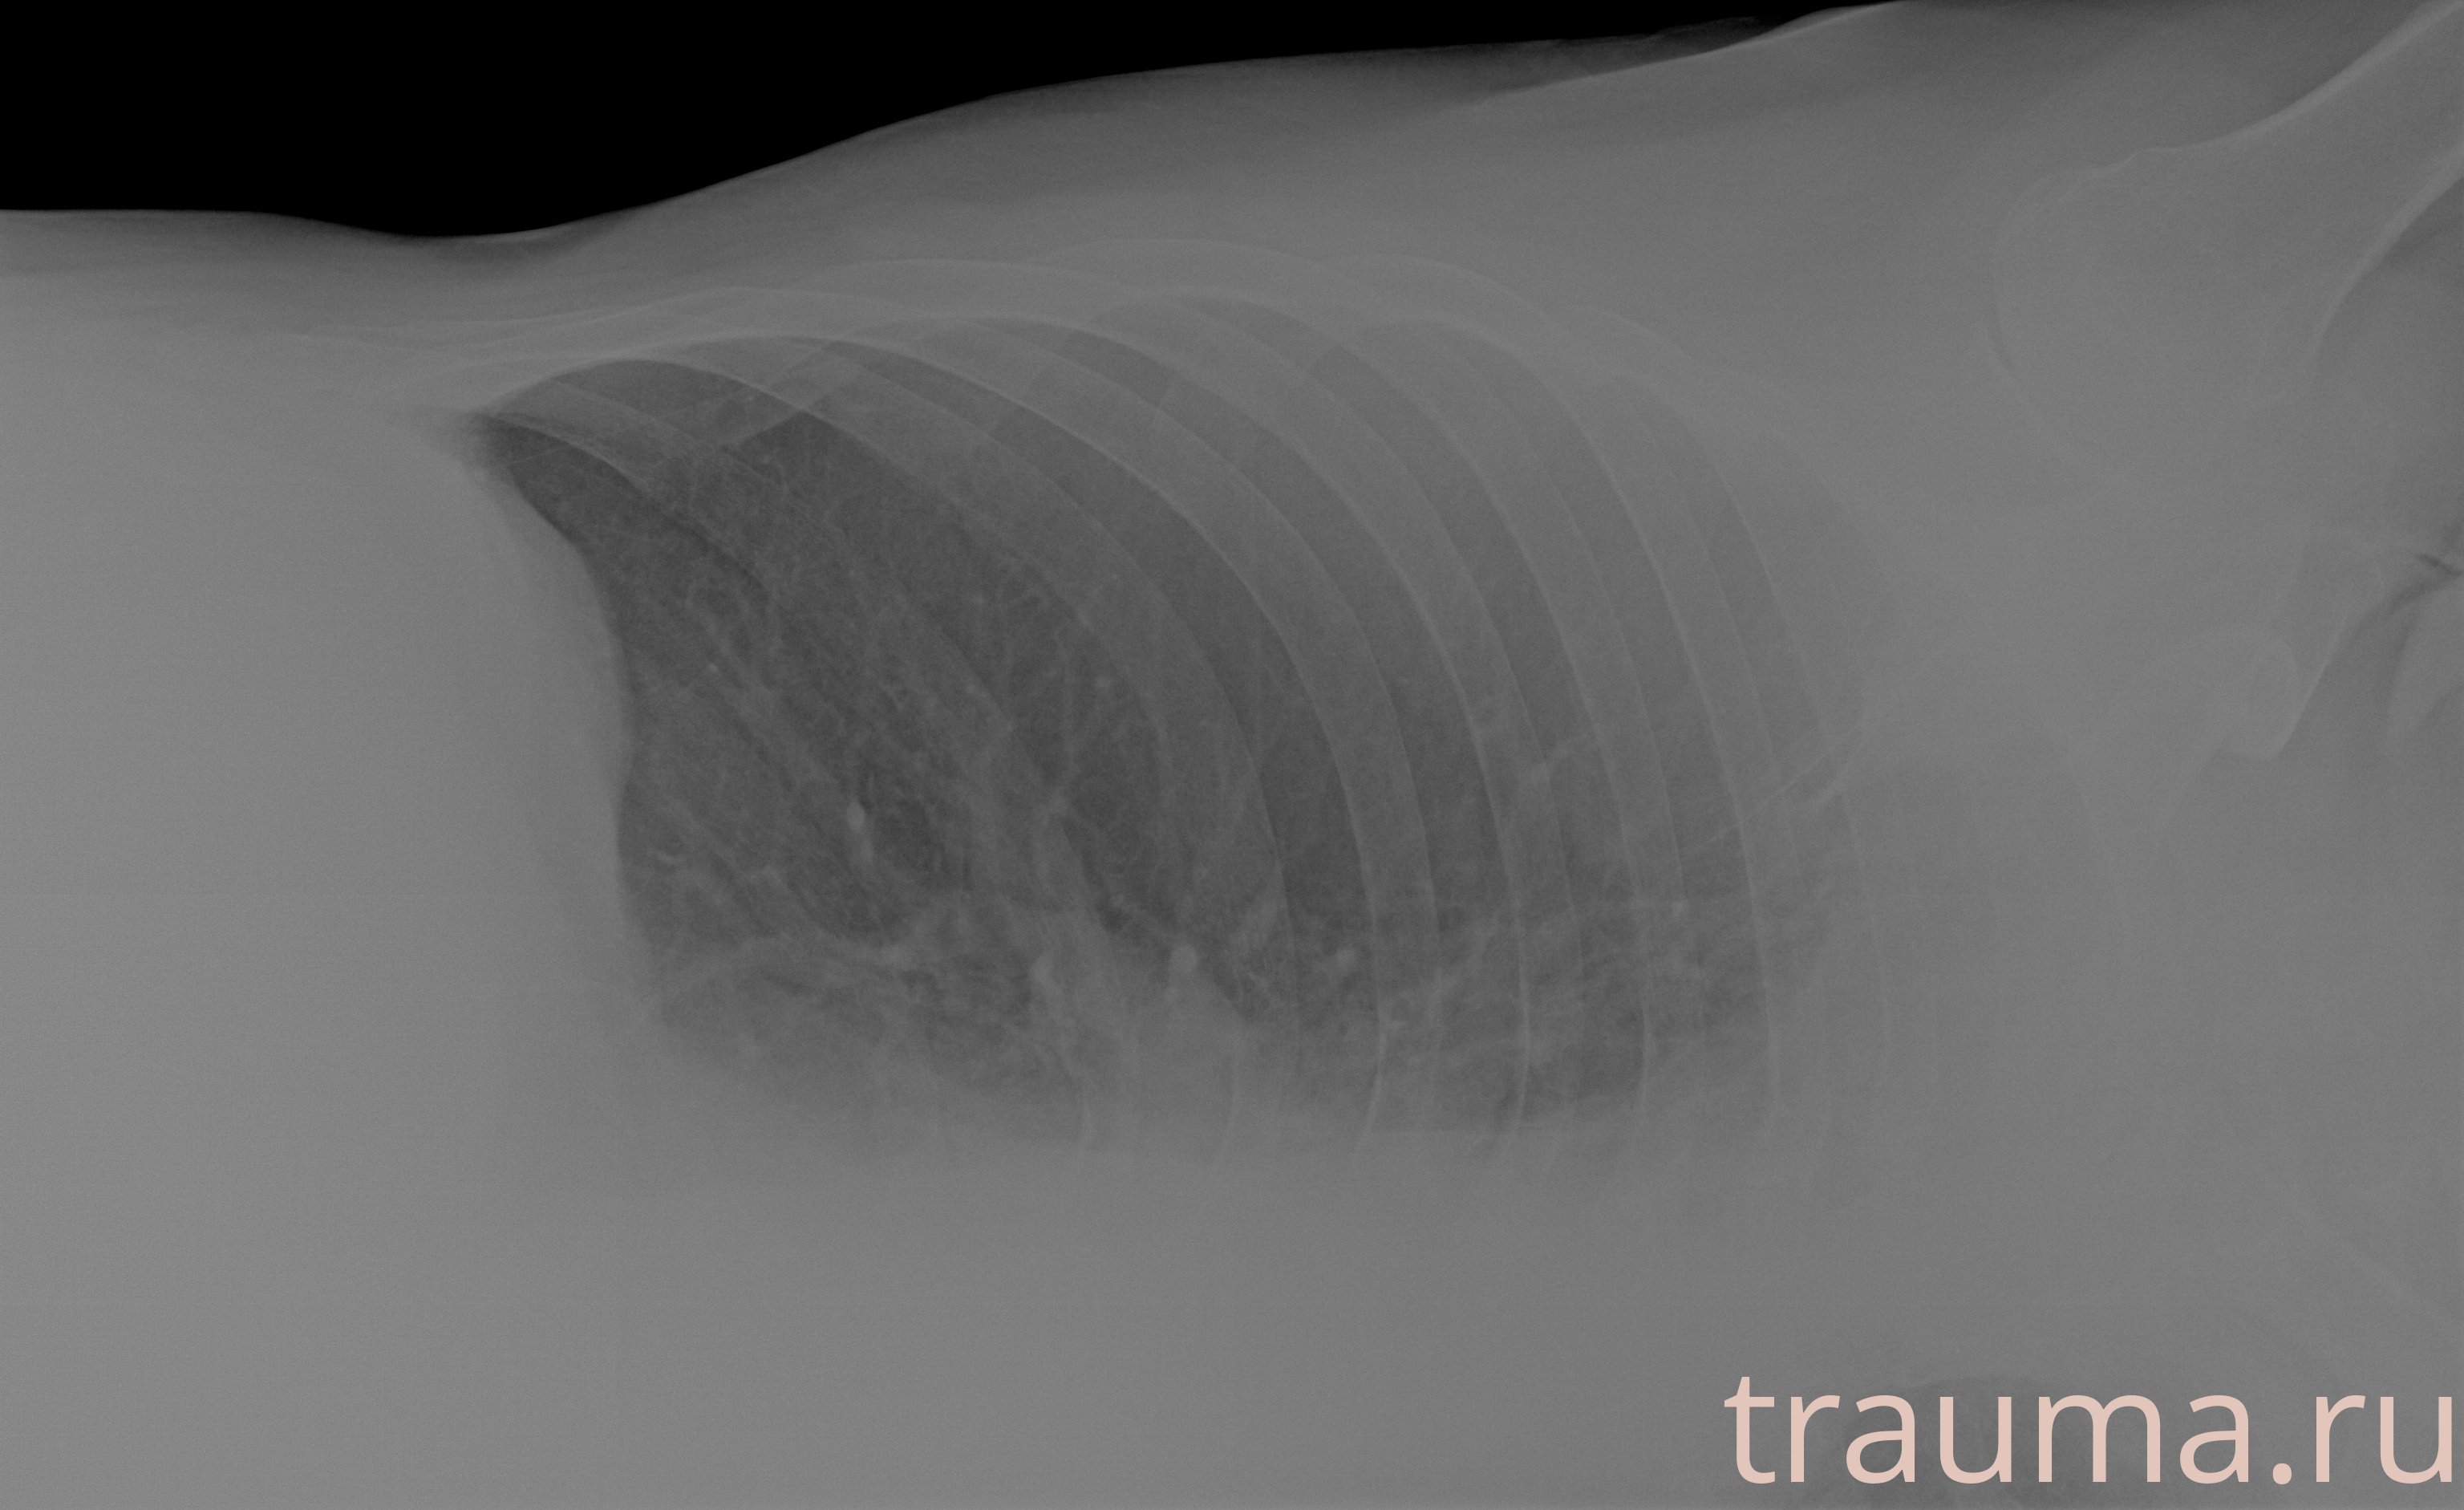

Рентгенограммы

Рентген на дому: по вашему адресу приезжает врач-рентгенолог, травматолог-ортопед с мобильным рентгеновским аппаратом, проводит диагностику травмы или заболевания, делает необходимые рентгенограммы, дает рекомендации по дальнейшему лечению. Получить качественные снимки в домашних условиях возможно благодаря уникальной методике, разработанной МосРентген Центром для института  Склифосовского

при переломе шейки бедра и пневмонии от компании МосРентген Центр - партнера Института имени Склифосовского